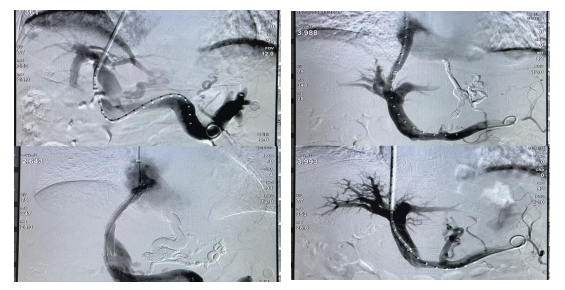

10月15日17时11分,在老年消化科与微创介入科团队的密切配合下,随着门-腔静脉通道的建立,曲张静脉的栓塞、门-腔静脉支架的置入,门静脉压力明显下降,历时将近3个小时手术顺利完成。患者全程清醒,无明显不适,术毕安返病房,术后造影可见支架内血流通畅,胃冠状静脉闭塞,栓塞良好。术后第2天陈思攀主任和吴友伟主任查房,患者出血停止,各项生命体征趋于平稳。手术的成功,标志着老年消化科在与兄弟科室合作下,对于肝硬化门脉高压症治疗领域又取得了新的佳绩。

附:TIPS术即经颈静脉肝内门腔分流术,是治疗肝硬化门脉高压症食管胃静脉曲张大出血的一种微创手术。在DSA引导下,通过穿刺及静脉支架,建立门静脉与肝静脉之间的通道,连接两大静脉系统,分流门静脉高压血流,达到降低门静脉高压及曲张静脉出血之目的,同时也有助于肝功能的恢复。